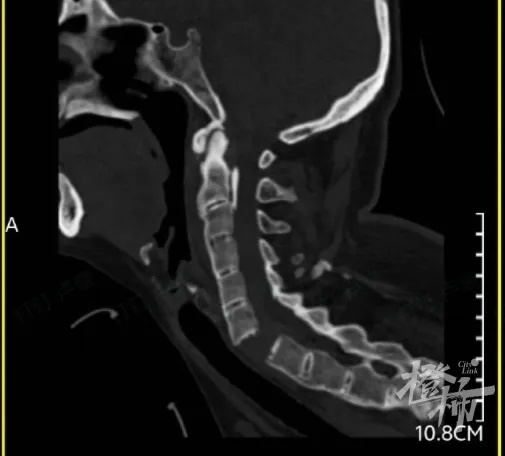

当时,刘女士出现颈部疼痛、四肢无力的症状,紧接着发现自己全身不能活动。随后,她被紧急送往附近的医院救治,通过颈椎影像检查后发现,刘女士颈椎6-7节完全断离,颈椎骨折造成脊髓损伤,导致全身瘫痪。

(检查发现,刘女士的颈椎完全断离)